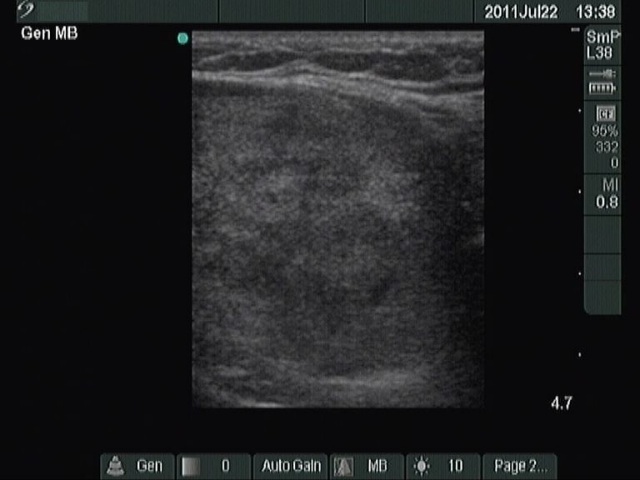

Benign nodular hyperplasia - Case 42. (ultrasonographic picture 5)

Right lobe, longitudinal scan

Left lobe, longitudinal scan. The lower pole of the lobe (right on the image) is not perfectly visible. It means that we cannot exclude the possibility of a substernal spread.